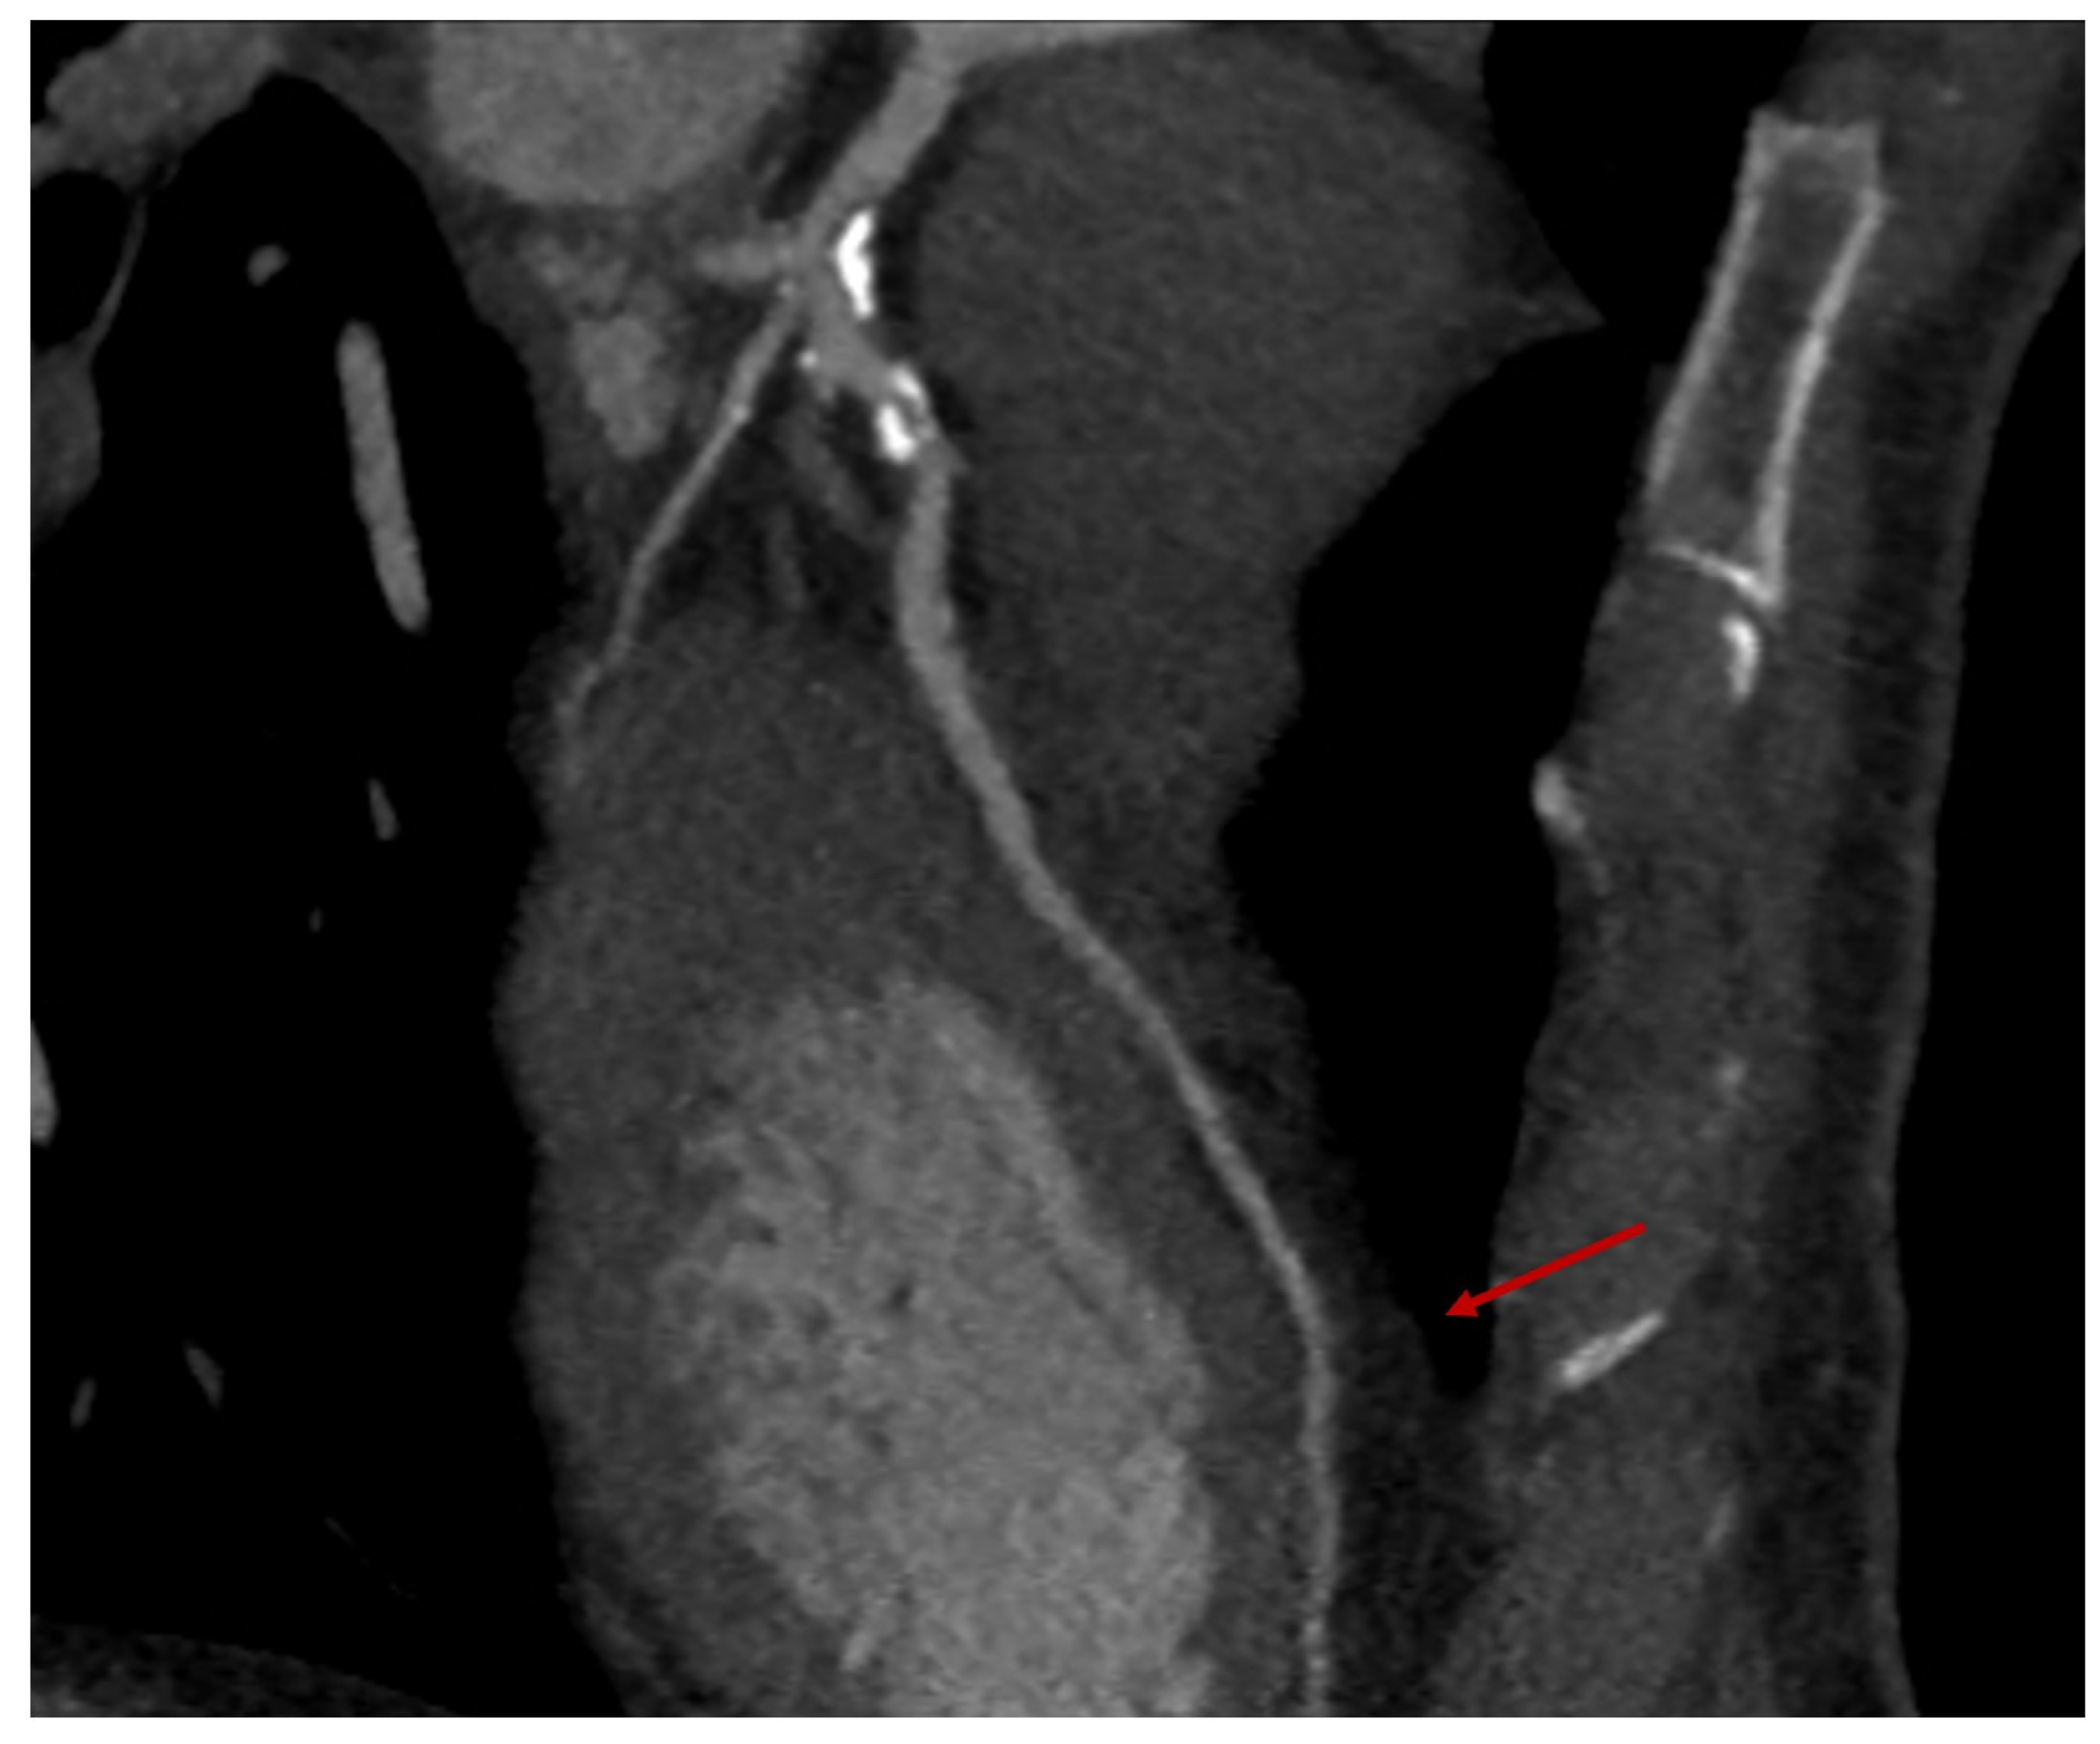

- Absence of calcification of the ascending aorta, allowing the execution of the proximal anastomosis (Figure 4A).